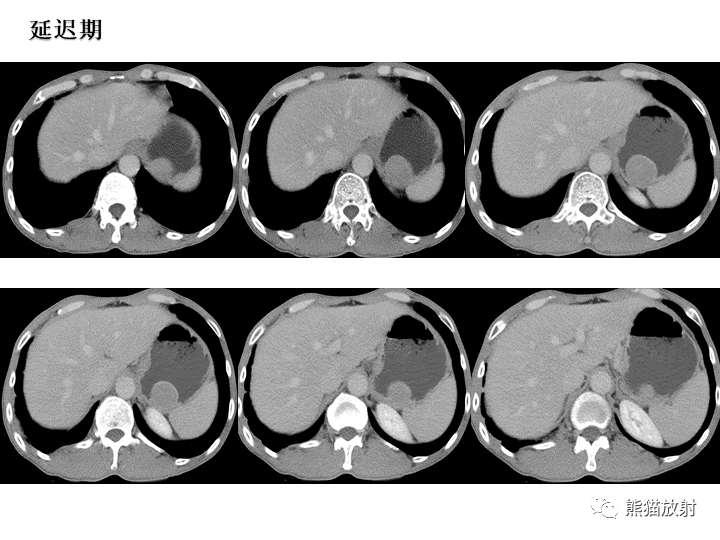

【病例】胃间质瘤VS神经鞘瘤-5